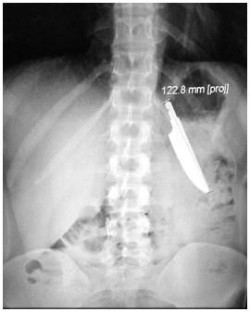

Abdomen supérieur avec un corps étranger.